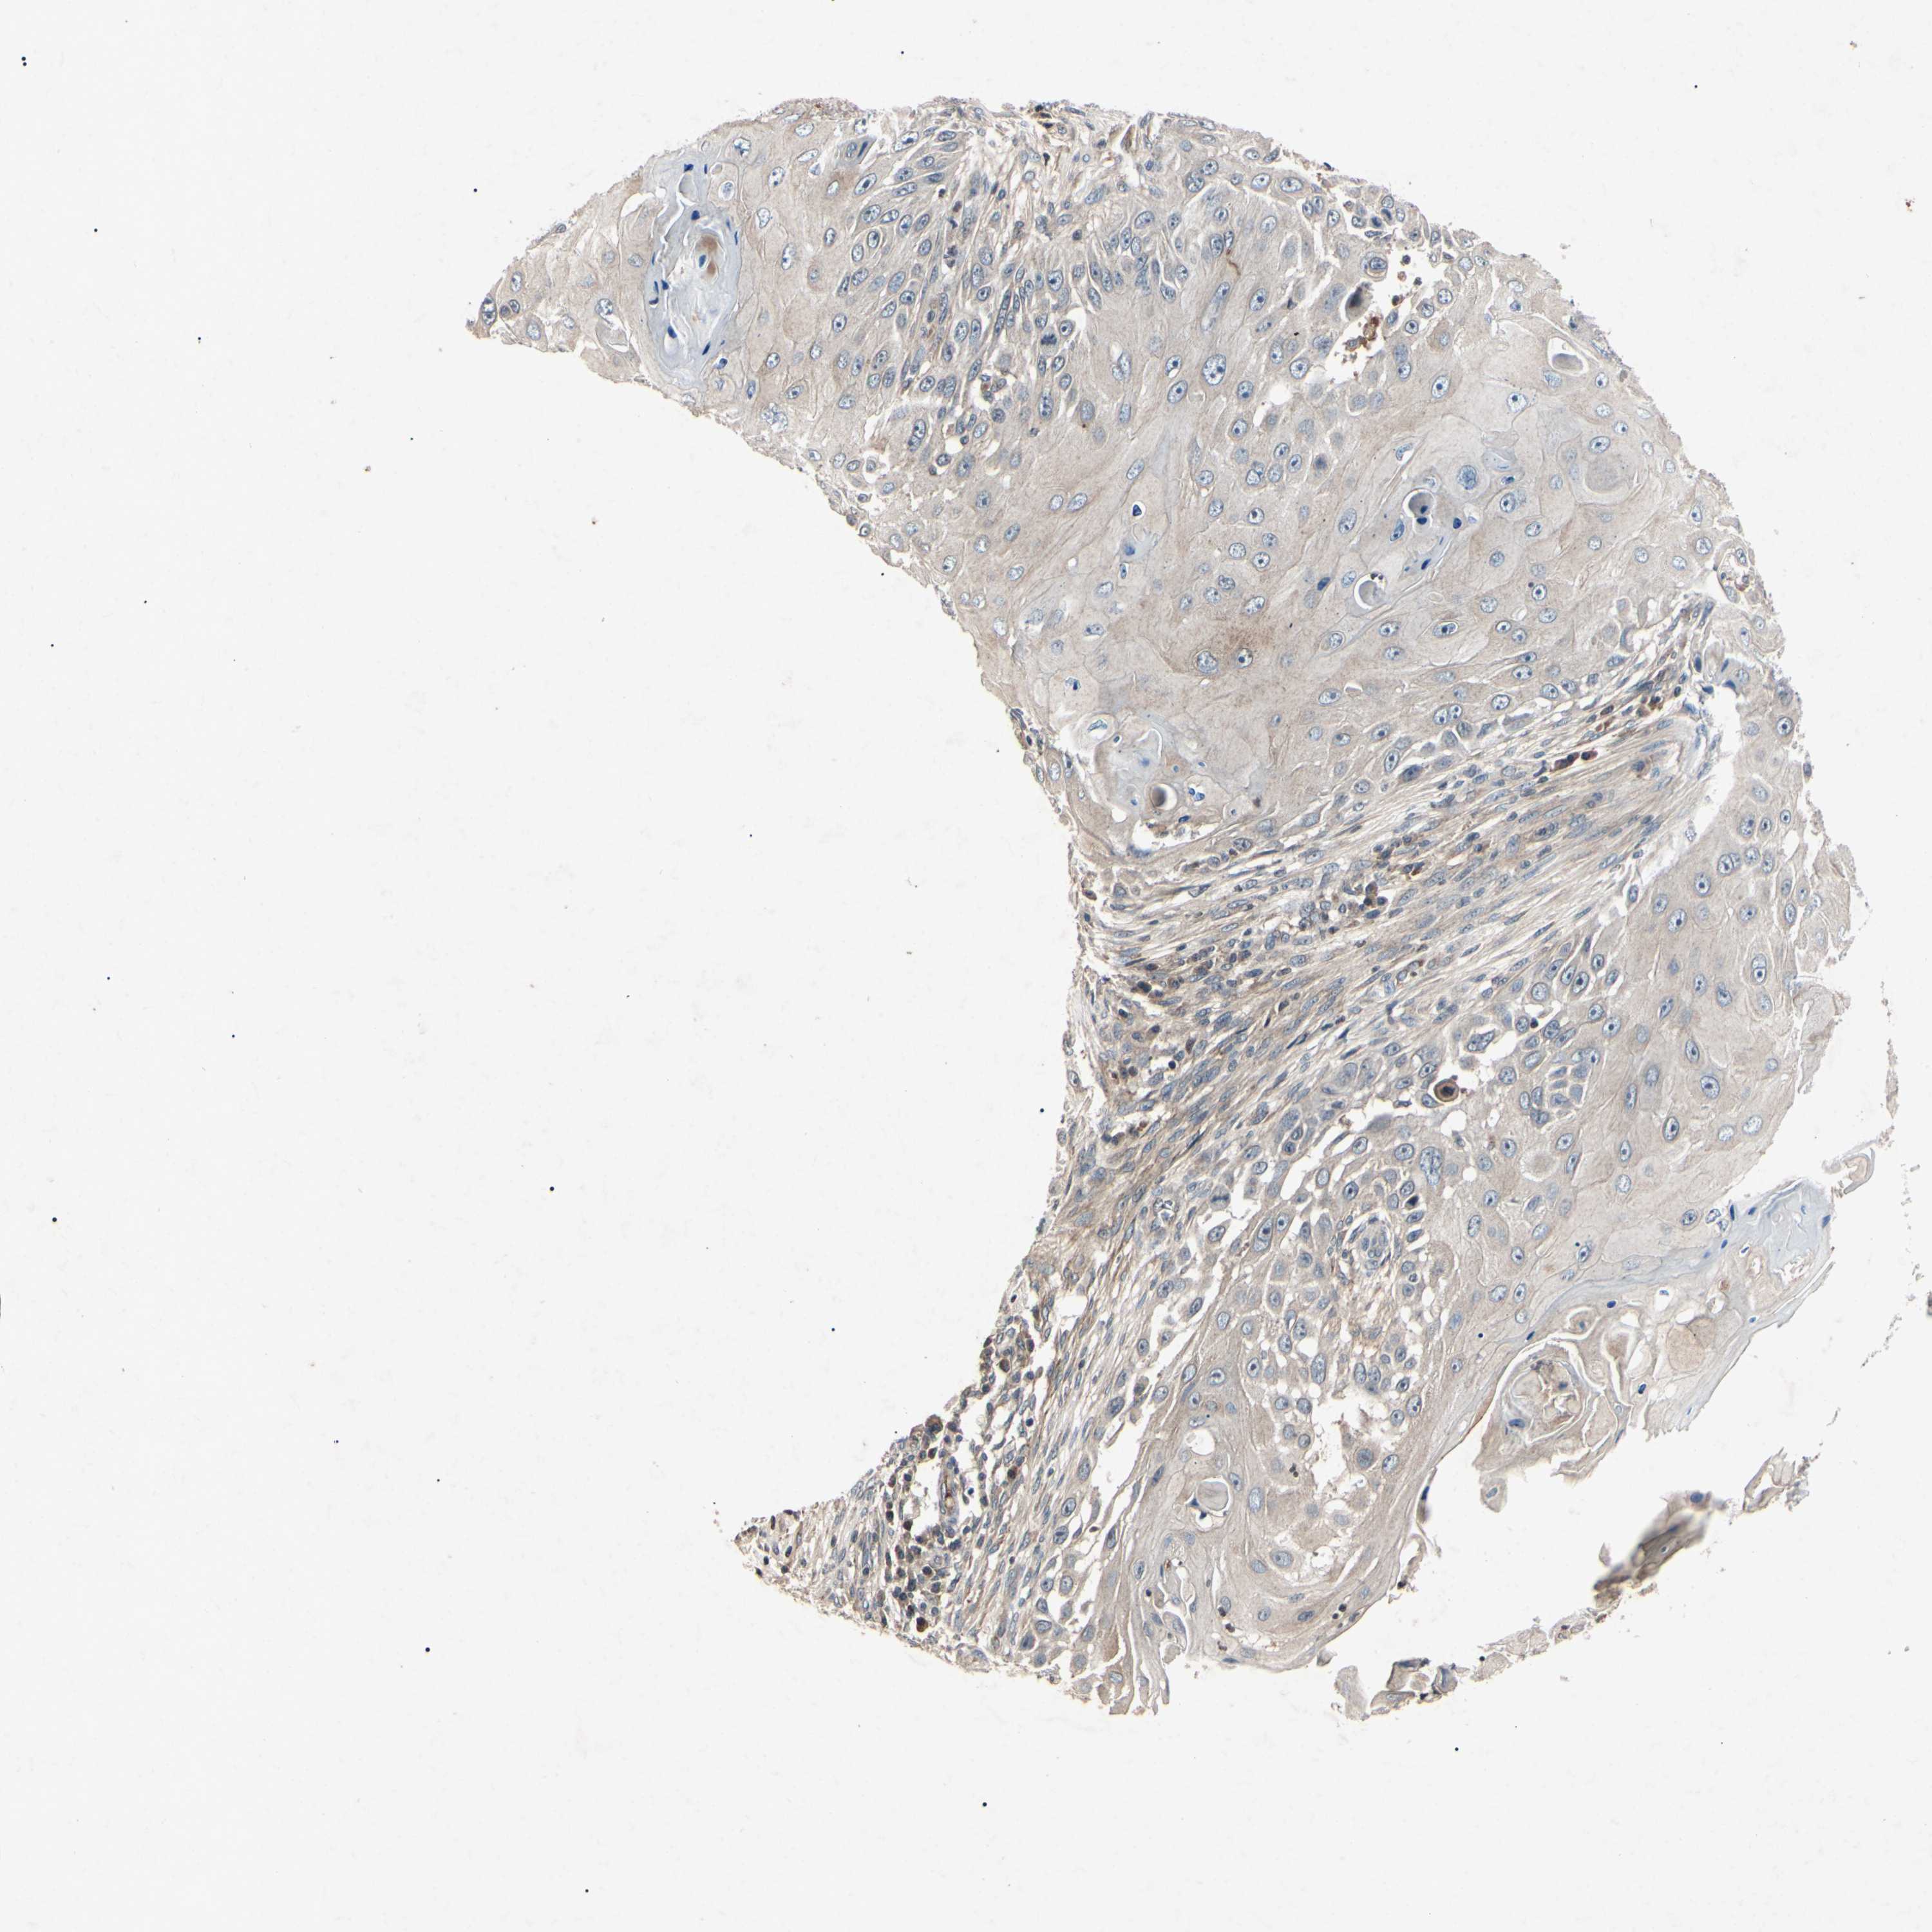

CANCER SKIN CANCER Show tissue menu

SKIN CANCER - Protein expressioni

A mouse-over function shows sample information and annotation data. Click on an image to view it in a full screen mode. Samples can be filtered based on level of antibody staining by selecting one or several of the following categories: high, medium, low and not detected. The assay and annotation is described here.

Antibody stainingi

Antibody staining in the annotated cell types in the current human tissue is reported as not detected, low, medium, or high, based on conventional immunohistochemistry profiling in selected tissues. This score is based on the combination of the staining intensity and fraction of stained cells.

Each image is clickable and will lead to virtual microscopy that enables deeper exploration of all samples and also displays staining intensity scores, fraction scores and subcellular localization as well as patient and tissue information for each sample.

Antibody HPA063595

Antibody HPA064970

Antibody CAB009966

Staining

High

Medium

Low

Not detected

Basal cell carcinoma

Squamous cell carcinoma, NOS